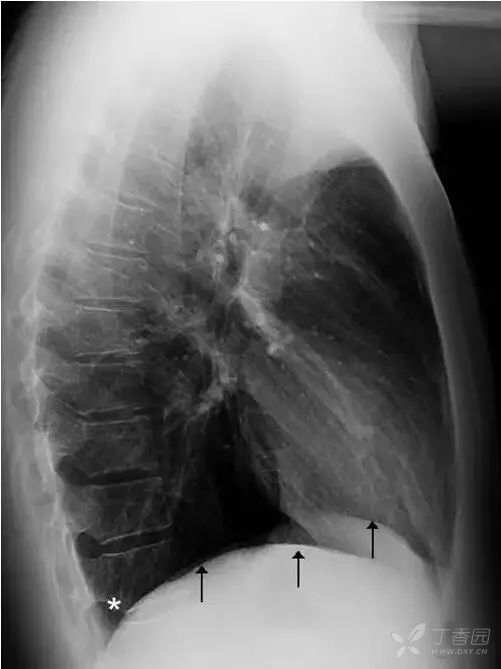

正常情况下,肋膈角是锐利的锐角。侧位胸片上(图18),横膈与前、后胸壁间分别形成前、后肋膈角。后肋膈角通常也是锐角,其位置在站立位为全肺最低处。

图18 侧位胸片上两侧横膈(黑色箭头)及后肋膈角(白色星号)。